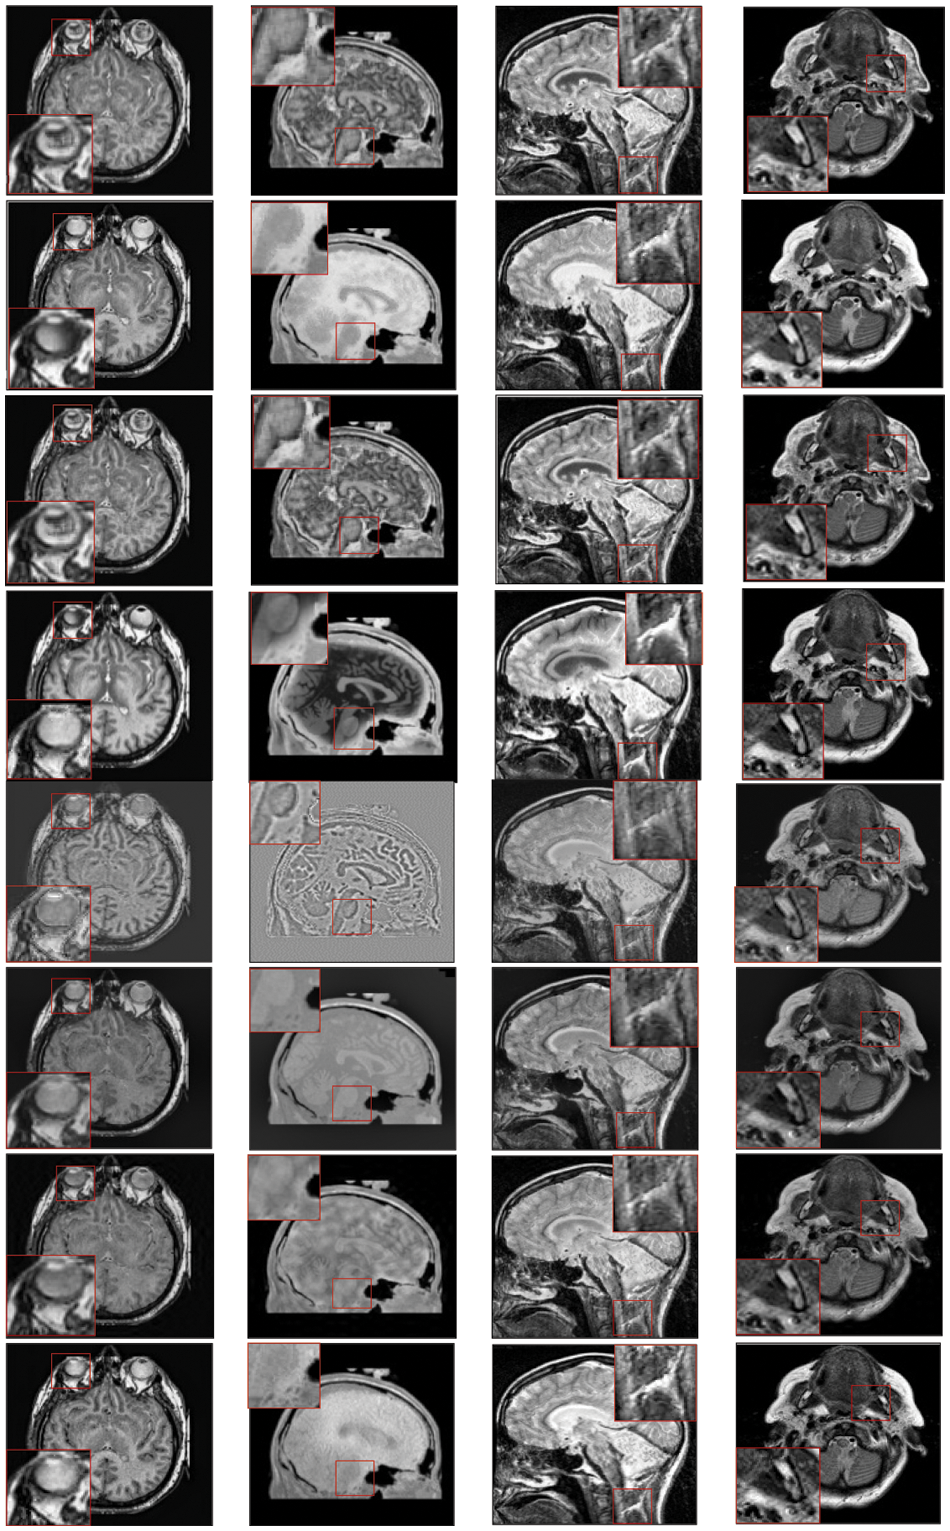

To investigate the efficiency of our proposed strategy, this study utilizes eight pairs of publicly accessible images from the Whole Brain Atlas [60]. The eight pairs of medical images in Figs. 2A–2H are represented by Set A to Set H, respectively. Statistical numeric indicators to validate the objective fusion performance is considered, including MI, H, API, CC, AG, API, SF, and SD. Further, in addition to the above metrics, an objective fusion characterization based on gradient details is also considered including

Figure 3: Qualitative results of CT-MRI image pairs on Set (A–D). From top to bottom: results by AISA-NSST, MIFDL, MDE-DNN, GADCT, MATM-HDF, SRSCNN, FDGNet and proposed algorithm

Figure 4: Qualitative results of CT-MRI image pairs on Set (E–F). From top to bottom: results by AISA-NSST, MIFDL, MDE-DNN, GADCT, MATM-HDF, SRSCNN, FDGNet and proposed algorithm

As per the experimental results, the outputs retrieved via the proposed method are very efficient and effective in the case of all quantitative parameters, whereas other algorithms yielded suboptimal values. Tables 1 and 2 show that our technique ranks first in simulation results for all dataset pairs when compared to other competing techniques. Even if a few parameters are higher with smaller margins than other methodologies, the differences in other parameters are higher. Further, the average result of these quantitative measures are shown in Tables 1 and 2 to provide a more intuitive grasp of quantitative evaluations in comparison to existing methodologies. In summary, the fusion results of the proposed algorithm outperform the existing seven comparative approaches in all aspects. Tables 1 and 2 exhibit indices incusing H, AG, SF, API, MI, SD, CC, and FS. At higher values of the above-mentioned metrics, the efficiency of the fused image is appropriate. Similarly, in addition to objective analysis, visual interpretation is more significant. Figs. 3 and 4 show the corresponding fused images to illustrate the performance visually. The proposed algorithm exhibits superior visual interpretation when compared to other methods. It also facilitates the process of testing other algorithms, which have comparably low experimental results. For the assessment of performance and to show the efficiency of our method, it observed that the effects of change in input for k,

Tables 3 and 4 show that our algorithm nearly always gets ideal values on all objective measures as compared to other competing algorithms that intuitively adapt to quality judgments. In summary, the fusion performance of our strategy surpasses all other algorithms in both qualitative interpretation and quantitative assessment. The overall performance measures of evaluation metrics are tabulated in Tables 1 and 2 where the fusion performances of our algorithm are superior with ideal scores in all these eight-objective metrics. The principal aim of image fusion is to produce an output that is highly suitable for human visualization with adequate, comprehensive, and detailed features in the fusion results. Further, visual interpretation is quite important, along with objective performance. The fusion results are demonstrated in Figs. 3 and 4 which interpret performance visually. The proposed approach has demonstrated superior visualization when compared to other comparable methods. The information transfer rate in the proposed technique is the highest when compared to other algorithms. according to the quantitative assessment in the case of gradient-based measures. In addition, the suggested method has a high